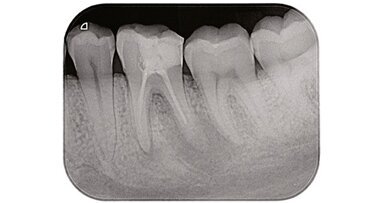

Il fallimento endodontico è un’evenienza che può capitare se rimangono batteri all’interno del sistema canalare come conseguenza di una insufficiente disinfezione, di un’inadeguata otturazione oppure quando viene meno il sigillo coronale1 (Fig. 1a). L’errore potrebbe essere risolto con successo grazie ad un ritrattamento per via ortograda2 oppure, se questo non è possibile, da un ritrattamento per via chirurgica.

Le tecniche non chirurgiche richiedono la completa rimozione del vecchio materiale da otturazione presente nello spazio endodontico al fine di ottenere una sagomatura, disinfezione e otturazione tridimensionale del sistema canalare più profonda e completa: condizioni indispensabili per ottenere il successo3 (Figg. 1b, 1c).